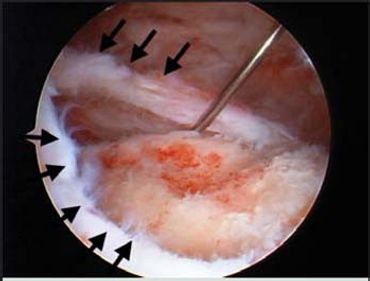

After an initial period of recovery, these exercises are designed to help you regain shoulder stability and prevent future dislocations.